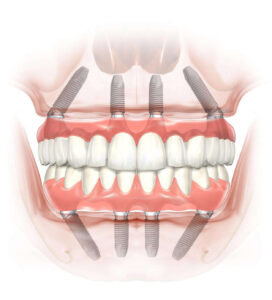

“All-on-4 feste Zähne” mit lebenslanger Garantie

Im Falle einer vollständigen Zahnlosigkeit sind All on 4 Implantatprothesen eine sofortige, langfristige und zuverlässige FIX-Lösung. Mit dieser schmerzfreien Behandlung gewinnen Sie Ihr jugendliches Lächeln, Ihr Selbstvertrauen und ein Lächeln, das Sie zum Lachen bringt, zurück.

Was ist diese “All-on-4”-Behandlung?

Bei völliger Zahnlosigkeit können wir über diese Technik sprechen, um eine schnelle FIX-Lösung zu finden. Es kann auch funktionieren, wenn Sie wegen einer Parodontalerkrankung oder aus anderen Gründen alle Ihre restlichen Zähne entfernen müssen. Je nach Größe des Kieferknochenbogens werden 4 oder bis zu 6 Implantate gesetzt, die bei ausreichender sogenannter Primärstabilität sofort mit einer provisorischen ästhetischen Brücke aus Kunststoff belastet werden. Damit entfällt die Notwendigkeit eines herausnehmbaren Zahnersatzes. Provisorische Zähne können innerhalb weniger Tage hergestellt werden.

Die Behandlung besteht hauptsächlich aus zwei Phasen:

- Implantate und provisorischer Zahnersatz

- Vorbereiten und Aufbau der endgültigen Zähne

Die SCHRITTE der All on 4 Implantatversorgungen: